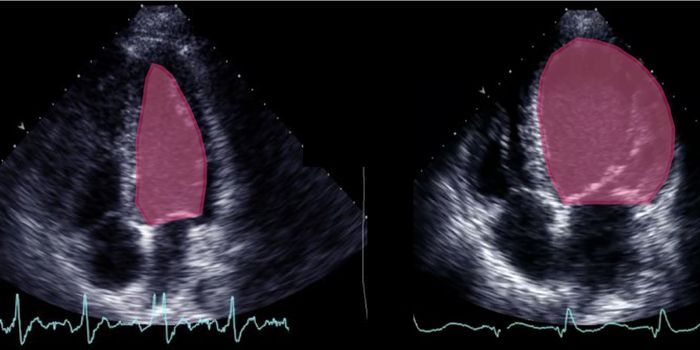

MAR 13, 2015CardiologyTo find out how blood flow in the heart shields against the hardening of valves in cardiovascular disease, researchers u ...

FEB 26, 2016CardiologyHeart disease is the leading cause of death nationally and globally. Using the most advanced 3D printing technology, sci ...